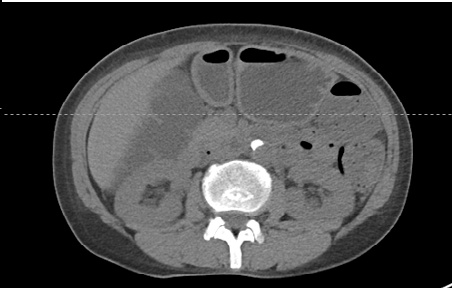

在处理医学图像时,常常会遇到以Dicom格式保存的医学图像,如CT、MRI等。Dicom文件是需要专门的软件或者通过编程,应用相应的库进行处理。为了能够更好地服务下游任务,例如分割或检测腹腔CT图像中某个病灶组织,需要先将Dicom图像进行读取,脱敏,调窗等步骤,以便于后续的编辑。本文使用python对医学Dicom文件进行相应的处理,相比于封装好的软件,笔者认为自己动手的可操作性更强。

设置CT图像的窗宽和窗位

return img_temp该函数的输入变量winwidth和wincenter即为需要设置的窗宽和窗位,这两个值根据研究的问题(不同的组织器官对应不同的窗宽和窗位,有时候也要根据图像效果进行一定的调整)调整不同的值。网上有很多关于相关的窗位和窗宽对应值,这里给出一些参考资料,如果遇到不确定的,最好借鉴查阅相应领域的论文。

结果保存及可视化

可以单张保存,或者批量处理。